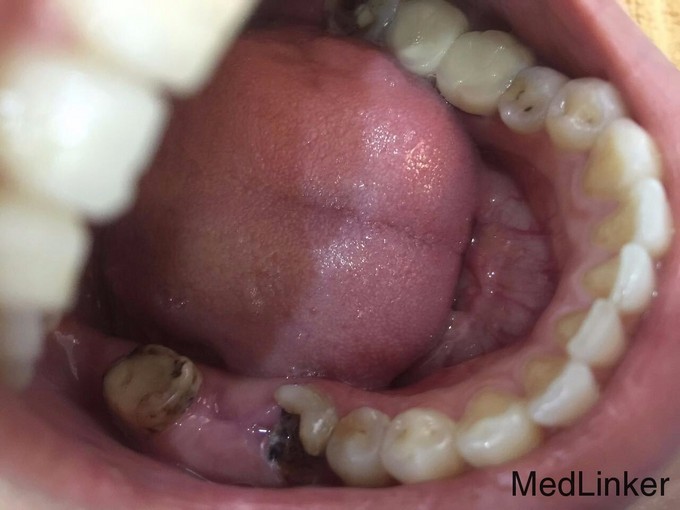

患者女40岁 后牙缺失 欲修复

后牙缺失 欲修复